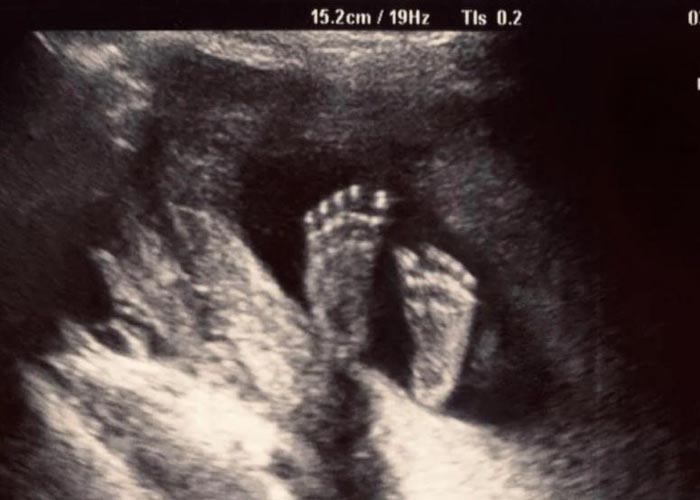

Durante las semanas 5-6 del embarazo “se desarrollan un corazón que late y un sistema circulatorio muy básicos”, se lee.

Anteriormente, Planned Parenthood se basaba en el Colegio Americano de Obstetras y Ginecólogos (ACOG), cuya “Guía sobre el lenguaje y el aborto” afirmaba que “el latido del corazón fetal sólo existe una vez que las cavidades del corazón se han desarrollado y pueden detectarse mediante ecografía, lo que suele ocurrir entre las semanas 17 y 20 de gestación”, informa National Review (NR).

Pero desde entonces el grupo se ha distanciado de la afirmación de ACOG escrita en una reciente nota a pie de página en una presentación ante un tribunal de Carolina del Sur que “Tras consultar con expertos”, el grupo “entiende que un corazón se forma antes de eso”.